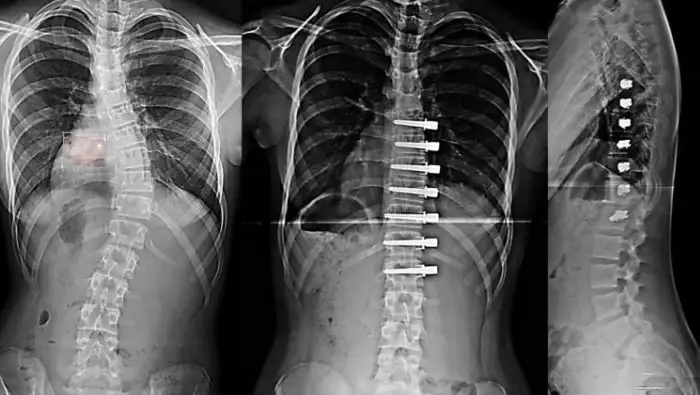

One of the problems in the surgical treatment of patients with Scoliosis, i.e. Spinal Curvature, is the fixation of the spine, thus eliminating spinal mobility in a certain area.

Thanks to the Tethering Method applied by Prof. Dr. Azmi HAMZAOĞLU and his team, this problem is eliminated. The patient’s spine movement is not destroyed. This provides an important advantage especially in pediatric patients. Because the growth of the child is not hindered.

In the spine of children treated with the Tethering Method, the growth in the concave direction continues, while the growth in the convex direction stops thanks to the rope attached to the screws. Thus, the curvature corrects itself over time. The operated area also retains its mobility.